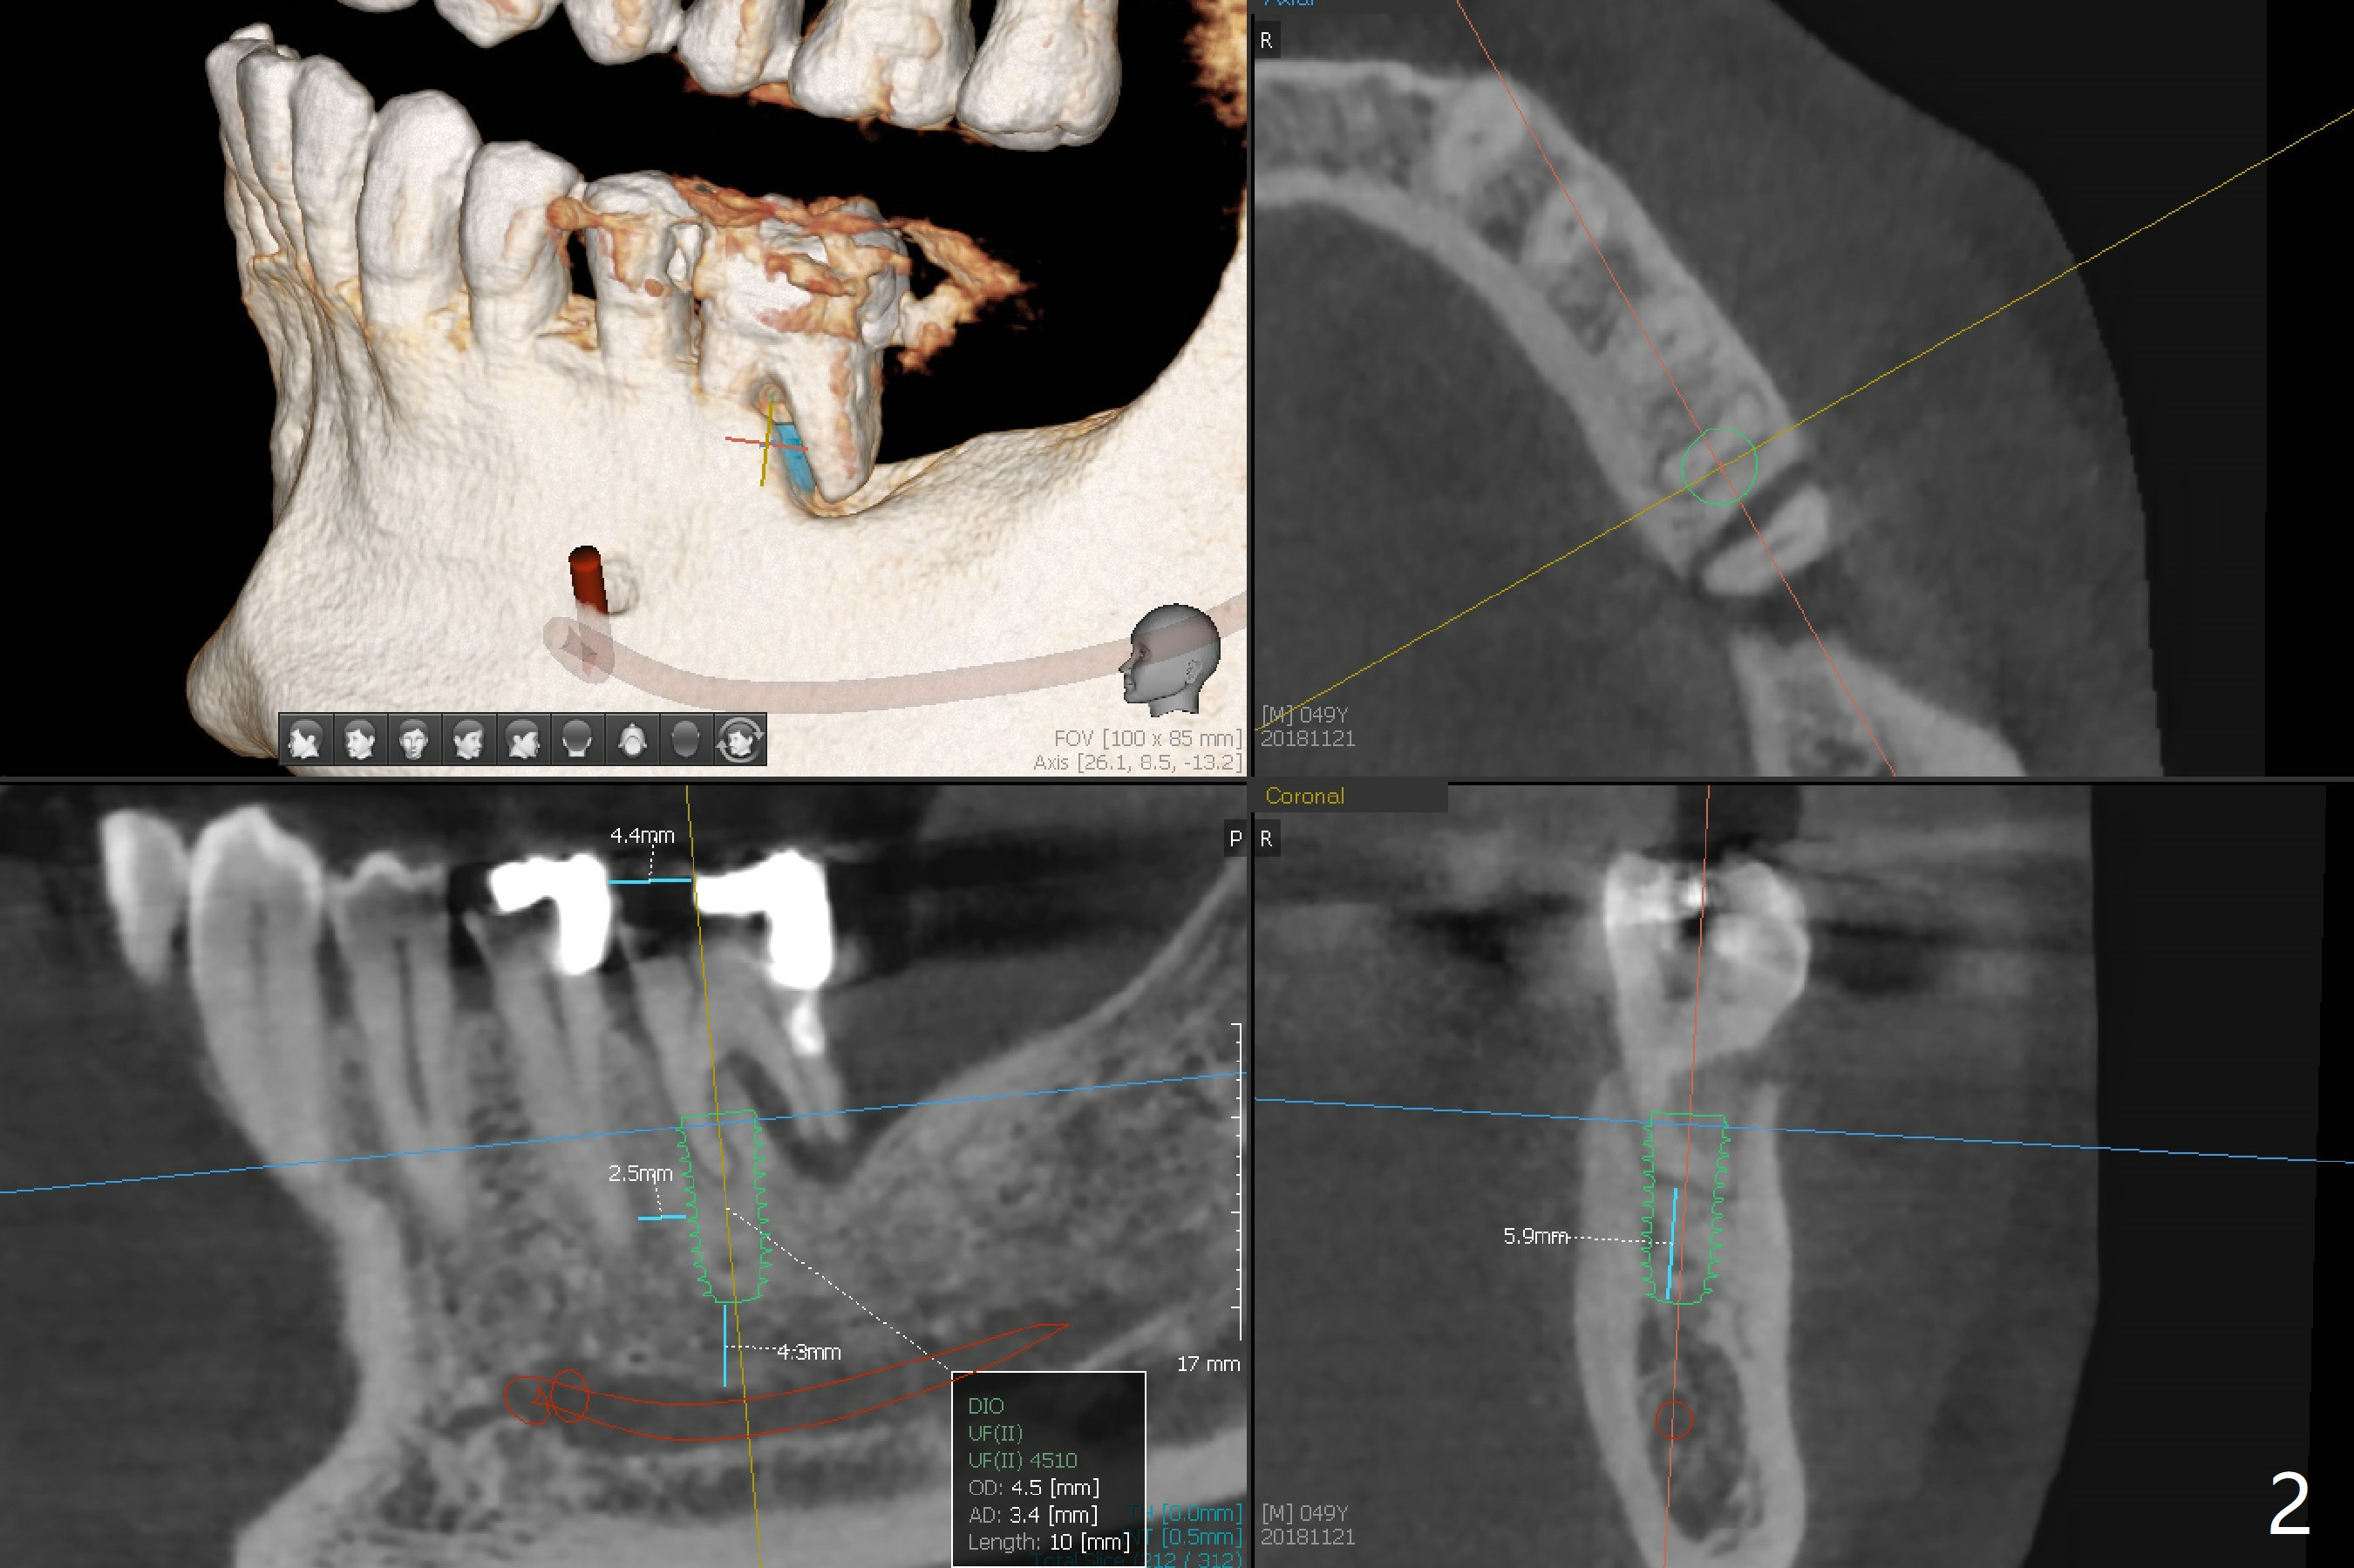

A 49-year-old man agrees to have #19 extracted for implant, 2 years 7 months and 2 years 10 months post cementation at #2 and 31, respectively (Fig.1). Because of severe bone loss in the distal socket of #19, a 4.5x10 mm implant will be placed in the mesial one (Fig.2). To reduce the chance of blockage of blood supply to the tooth #20 (Fig.3 red curved line), the implant will be not placed deep. After osteotomy with guide, a 1.5 mm longer implant will be chosen if there is extra coronal bone as shown in Fig.3 (3D image (white line)).